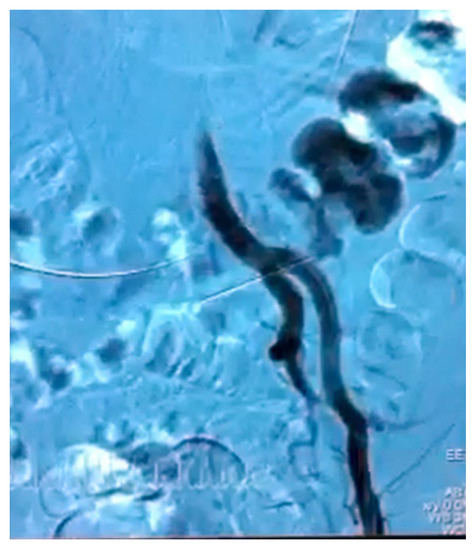

| Angiography | 5/7 (71.42) |

| Fistula location | |

| Left ureter–left CIA | 6/9 (66.66) |

| Left ureter–abdominal aorta | 1/9 (11.11) |

| Left ureter–EIA–descending colon | 1/9 (11.11) |

| Right ureter–right CIA | 1/9 (11.11) |

| 1 | 2012 | Negative | Positive | USC | Left ureter- left CIA | Endovascular stent | Nephrostomy | endovascular restenting | 7 | Dead | |

| 2 | 2013 | Negative | N/A | USC | Left ureter- Aorta | Aortic patch | Nephroureterectomy | 1 | Dead | ||

| 3 | 2015 | Positive | Positive | USC | Left ureter- left EIA+ colon | EIA ligation and FFC | ureter ligation +Nephrostomy | Left colectomy | 78 | Dead | |

| 4 | 2016 | Positive | Positive | USC | Left ureter- left CIA | CIA ligation and FFC | ureter ligation +Nephrostomy | 64 | Alive | ||

| 5 | 2018 | Positive | Negative | USC | Left ureter- left CIA | Endovascular stent | Nephrostomy | Nephrectomy | 32 | Alive | |

| 6 | 2019 | Negative | N/A | UPR | None | Left ureter- left CIA | Patch angioplasty | Nephroureterectomy | 27 | Alive | |

| 7 | 2020 | Positive | Negative | Bricker | Left ureter- left CIA | Endovascular stent | Nephrostomy | endovascular restenting | |||

| 2021 | Negative | Negative | Right ureter- right CIA | Endovascular stent | Nephrostomy | Ureter ligation +CIA ligation and FFC | 4 | Dead | |||

| 8 | 2021 | Negative | Positive | Bricker | Left ureter- left CIA | Endovascular stent | Nephrostomy | 10 | Alive | ||

| 9 | 2021 | Positive | Positive | USC | Left ureter- left CIA | Endovascular stent | Nephrostomy | 8 | Alive | ||